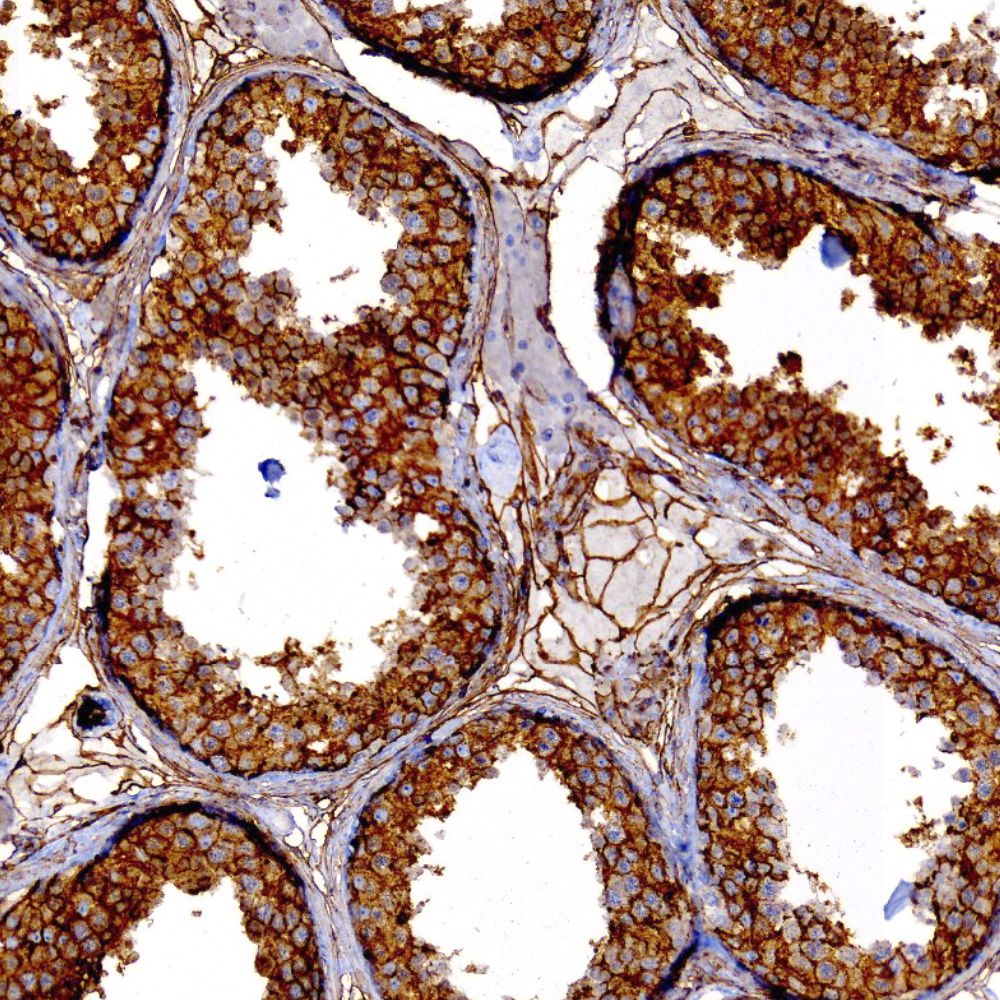

Sexcord stromal tumor stained with Anti-CD99

CD99 is a transmembrane glycoprotein, also known as MIC2. It is involved in T-cell adhesion, leukocyte migration and differentiation of primitive neuroectodermal cell. CD99 labels lymphocyte, ovarian granulosa cells, pancreatic islet cells, sertoli cells, CNS ependymal cells and endothelial cells. CD99 has been useful in diagnosis of Ewing's sarcoma, sex cord-stromal tumor, and endocrine tumor of pancreas. Additionally, it is found in a subset of other tumors including lymphoblastic lymphoma, breast carcinoma and other malignancies.